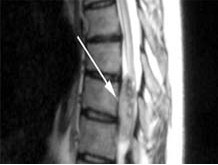

椎管内肿瘤 椎管内肿瘤术中